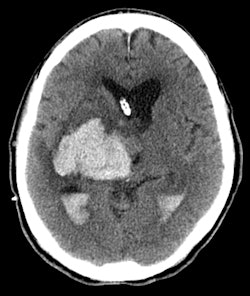

Head CT scans are routinely ordered on these patients to assess for emergent findings such as new or worsening stroke, hydrocephalus, brain herniation, or bleeding. But the decision to scan can be tricky territory.

Part 1 of the project, a study in press in Critical Care Medicine, focused on nearly 2,500 CT scans performed on 1,357 patients in the ICU with a diagnosis of altered mental status. The researchers looked for abnormal results such as new or worsening hemorrhage, stroke or infarct, hydrocephalus, or brain herniation.